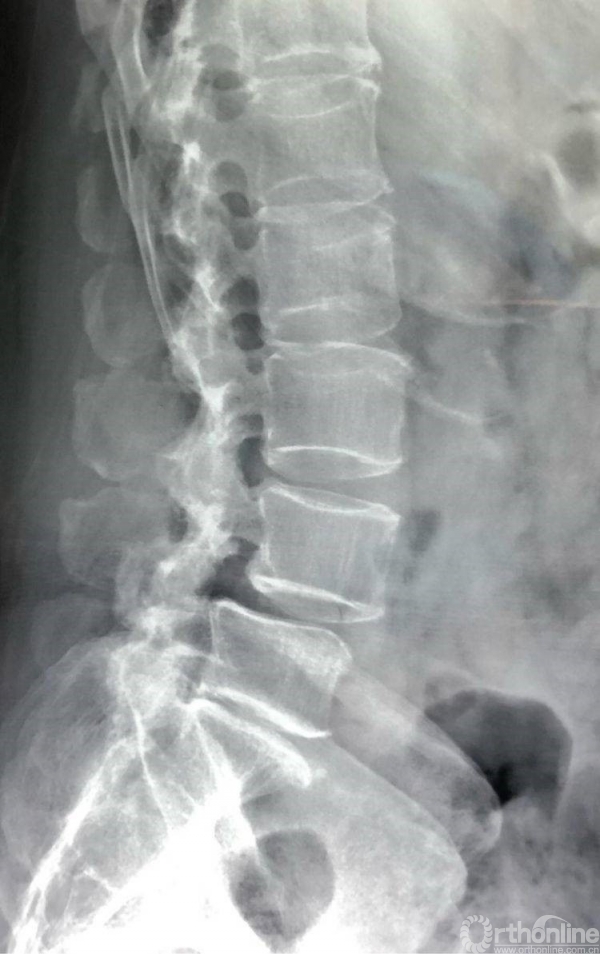

术前CT示L4/5重度椎管狭窄,腰椎滑脱合并硬膜囊受压。辅助检查如下:

侧位X片